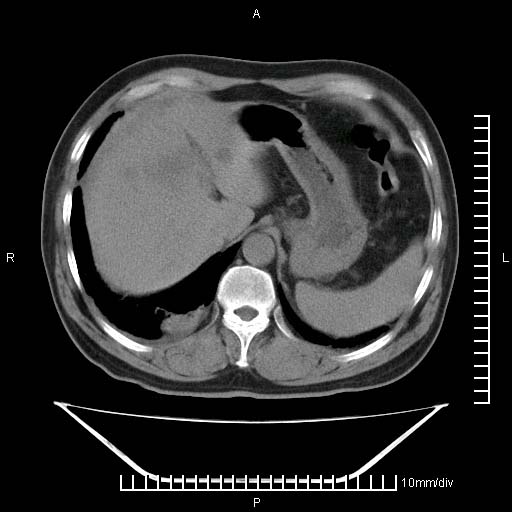

标题: CT25082:肝脏增强:男性,70岁 [打印本页]

标题: CT25082:肝脏增强:男性,70岁

患者以心脏疾病收住院,腹部无明显症状,b超查肝脏有占位。

增强效果不理想。考虑转移,胆囊壁明显增厚,不排除胆囊癌肝转移。

牛眼征,中心坏死无强化,外缘强化,最外缘又见低密度,考虑转移,与脓肿鉴别

考虑右肺下叶周围癌肝转移

肝内多发转移瘤,右下肺炎症并少量胸水。胃壁增厚建议胃镜,胰尾部“病变”为肠管。

1)肝脏多发性转移瘤(不排除胰尾癌转移所致可能)。2)腹水。3)右侧少量胸腔积液。

ct25082 结果:转移瘤

外院mr结果:胰尾恶性占位。